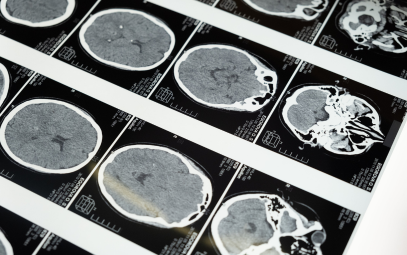

Listening to the Injured Brain: How Brain Computer Interfaces Are Transforming Neurocritical Care

When caring for patients with severe brain injury, silence can be one of the hardest parts of the ICU. A patient lies still, ventilated, eyes closed, and we’re left wondering: what is their brain trying to tell us?

In recent years, brain computer interfaces (BCIs) have begun offering an answer. Once confined to neuroscience labs, these systems are now finding their way into neurocritical care, helping clinicians detect covert consciousness, refine sedation management, and even prognosticate outcomes.